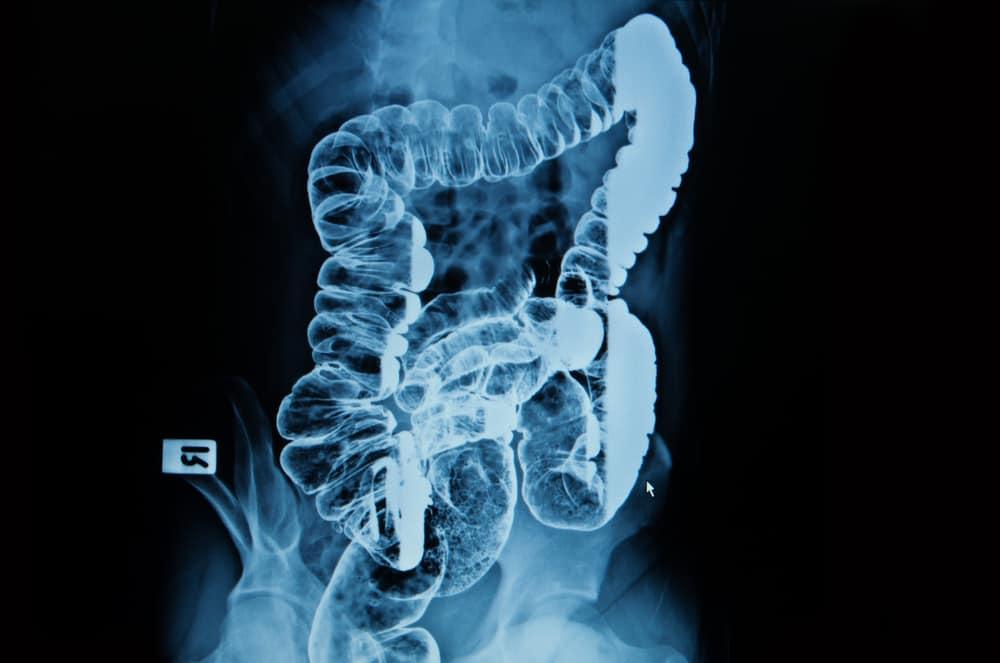

Kentut merupakan cara alami tubuh untuk membuang limbah dalam bentuk gas. Bahkan terkadang kita mengeluarkan kentut bau busuk yang cukup mengganggu. Sebenarnya, apa penyebab kentut bau busuk dan apakah ada cara untuk mengatasinya? Temukan jawabannya di penjelasan berikut yuk! Penyebab kentut bau busuk Salah satu fungsi sistem pencernaan manusia adalah mengeluarkan gas di perut yang sering disebut kentut. Menurut […]